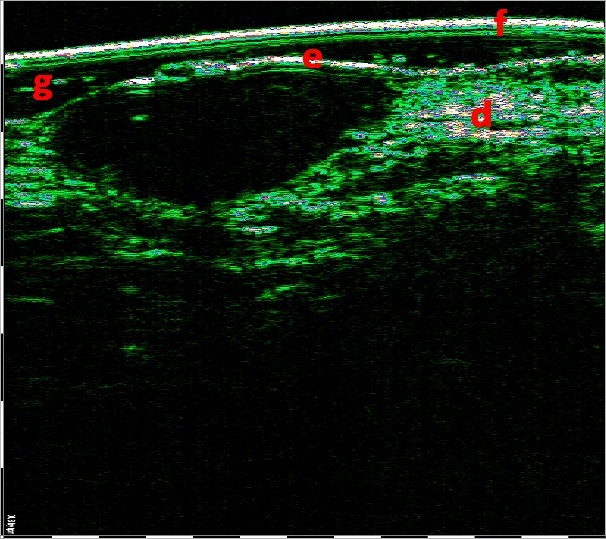

Φλύκταινες (1η εικόνα) και συνδυασμός οζιδίων και κυστών (2η εικόνα). Οι πιο έντονες αλλαγές εντοπίζονται στο πάχος του χορίου. Σαρώσεις με Υπέρηχο Υψηλής Συχνότητας και Βιντεοδερματοσκοπικές απεικονίσεις.

ΕΚΤΙΜΗΣΗ ΤΗΣ ΣΟΒΑΡΟΤΗΤΑΣ ΤΗΣ ΑΚΜΗΣ

Η εξέταση ακμής με HFUS είναι χρήσιμη για την ακριβή διάγνωση της μορφής της ακμής {φλεγμονώδης/μη φλεγμονώδης, φλύκταινες, συνεστιώδης : βαθιά φλεγμονώδη οζίδια, αποστήματα και συρίγγια που συνδέονται κάτω από το δέρμα, δημιουργώντας ομάδες βλαβών κυρίως στον κορμό και στους γλουτούς, αφήνοντας ουλές) κ.λπ.}.

Για παράδειγμα, η σοβαρότητα της ακμής πολύ συχνά υποτιμάται, επειδή οι εσωτερικές αλλαγές στο χόριο και κάτω είναι αόρατες.

Η εξέταση με HFUS επιτρέπει την εμφάνιση των σημείων διήθησης, εξίδρωσης και ίνωσης, γεγονός που επιτρέπει τη διάγνωση του τύπου της ακμής και την εφαρμογή της κατάλληλης θεραπείας, με έλεγχο της αποτελεσματικότητας της θεραπείας με HFUS.